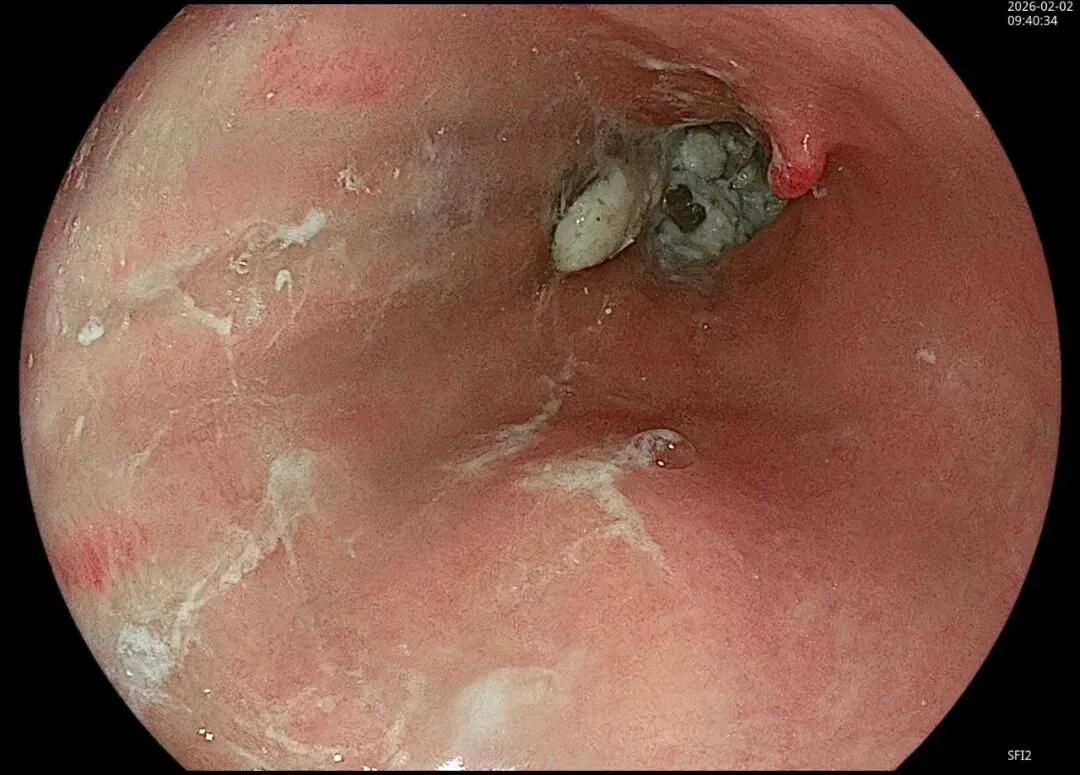

这一期不用码字,挺好的,很可惜一直没机会听过胡导讲的关于这个“花环征”的大课,学习内容来源于雨夜大师的号花环征:AIG背景的胃食管结合部的黄色颗粒状隆起及半透明“泡状”改变

补充自己在两例A型胃炎/AIG 观察到的“花环征”,巩固下学习效果。。。

case2:(made in china机子)👇

1.白光表现为胃食管交界处黄色颗粒状隆起及半透明“泡状”改变

2.窄带光下可见颗粒状隆起呈褐色改变,放大可见细微网状血管结构及半透明“泡状”改变

3.典型病理是鳞状上皮局灶性变薄及黏膜固有层显著增生、扩张的贲门腺。